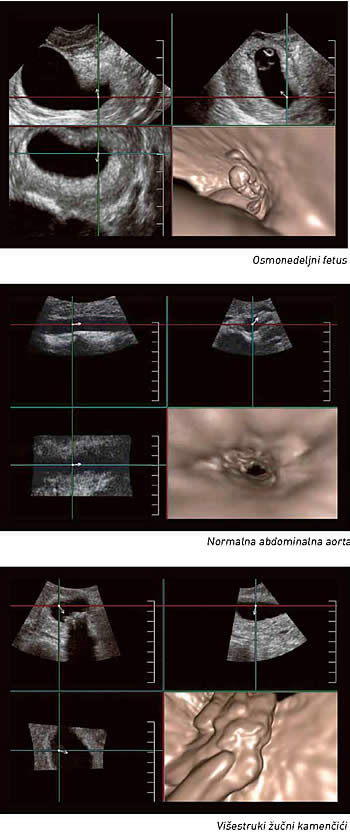

Virtuelna ultrazvučna endoskopija

Jedna od novih mogućnosti ultrazvučne tehnologija je FlyThru modalitet, koji omogućava jedinstvene adaptacije 4D imidžinga i daje endoskopsku sliku, ali bez interventne, invazivne procedure

Da će ultrazvuk nesumnjivo očuvati, ali i proširiti svoje suvereno mesto u dijagnostici uopšte, dokaz je jedan novi ultrazvučni sistem, koji predstavlja gospodin Andreja Gvozdenović, inženjer i stručnjak za medicinsku opremu u beogradskom “Beolaser”-u. Reč je sistemu komercijalno nazvanom Aplio 500 , koji je razvila kompanija “Tošiba”, a koji karakteriše niz naprednih mogućnosti vizualizacije. Jedna od tih novih mogućnosti je i tehnologija koju su njeni tvorci nazvali FlyThru , i koja je prva te vrste u ultrazvučnim dijagnostičkim sistemima uopšte. Baš kao što joj ime kaže, ona omogućava dijagnostičaru da 4D ultrazvučnom slikom virtuelno “leti kroz” unutrašnjost telesnih šupljina i krvnih sudova.

Reč je sasvim novoj perspektivi posmatranja telesnih struktura i slici koja je drugačija od svega poznatog u dosadašnjem ultrazvučnom imidžingu. FlyThru slika, naime, virtuelno putuje kroz telesnu šupljinu slično kao kod CT, odnosno slična je skenerskom prikazu. Gospodin Gvozdenović objašnjava da tipičan 4D imidžing koristi tzv. paralelnu projekciju posmatranog objekta, što onemogućava sagledavanje njegove “dubine” ili posmatranje prostora okolo tog objekta. FlyThru međutim, koristi perspektivnu projekciju, pa je dobijena slika identična kao u endoskopskim procedurama. Budući da su klasične endoskopske procedure invazivne, za pacijenta krajnje komforan ultrazvučni pregled, koji pri tom daje endoskopsku sliku, od ogromnog je značaja.

Osim što će u dijagnostici moći da zameni ili dopuni mnoge endoskopske procedure, FlyThru tehnologija obezbeđuje sliku izuzetne oštrine i jasnoće, te njene mogućnosti zapravo tek počinju da se istražuju u praksi. Ono što se sa sigurnošću sada može reći jeste da će FlyThru biti od ogromnog značaja u svim granama medicine. U ginekologiji, na primer, jedna od uzbudljivih mogućnosti je virtuelna histeroskopija. Ultrazvučni režim rada omogućiće da se polipi, miomi, srasline u materici ili bilo šta drugo unutar materične šupljine posmatra na sasvim nov način. Dva jedinstvena načina za korišćenje FlyThru u virtuelnoj histeroskopiji uključuju identifikovanje polipa i manipulisanje slikom tako da se polipi mogu videti i otpozadi, kao i procenjivanje stanja jajovoda, što je tradicionalnom histeroskopijom teško izvodljivo.

Naprednija dijagnostika

FlyThru omogućava da se vide i relativno male, fluidom ispunjene strukture od svega nekoliko milimetara, kao što su, na primer, prošireni kanali u dojci, što bi pomoglo u dijagnostikovanju intraduktalnih papiloma. U perinatologiji, u praćenju rane trudnoće, mogle bi se dijagnostikovati fetalne anomalije kao što su rascepljena (“zečja”) usna i druge anomalije lica. Imidžing neonatalne glave ovom novom metodom takođe je potpuno jedinstven način pregleda hidrocefalusa kod novorođenčadi.

Gastrointestinalni trakt takođe je polje gde bi se nova tehnologija mogla pokazati suverenom. Sposobna je, naime, da vizualizuje pankreasni kanal, žučnu kesu ili creva. Hidronefroze, kamen, opstrukcije, karcinomi tranzicionih ćelija ili čak lezije bešike vrlo kvalitetno se mogu ocenjivati putem FlyThru . Kad je reč o snimanju debelog creva , FlyThru daje slike veoma slične virtuelnoj kolonoskopiji (skenerskom pregledu debelog creva).

Venski sistem se, takođe, veoma jednostavno i kvalitetno može pregledati uz pomoć FlyThru . Mogu se uočiti venske tromboze, stenoze hepatičnih vena, ugrušci u perifernim venama. Kad je reč o aorti, tehnologija je jedinstvena po tome što može dati sliku sličnu intravaskularnom ultrazvuku, ali bez izvođenja interventne procedure.

FlyThru ne samo što obezbeđuje izvanredan imidžing već potencijalno može značajno da unapredi dijagnostiku mnogih oboljenja, zaključuje Andreja Gvozdenović. Zahvaljujući jedinstvenim mogućnostima adaptacije 4D, slika koju daje FlyThru potpuno je nova i jedinstvena u ultrazvučnoj tehnologiji.